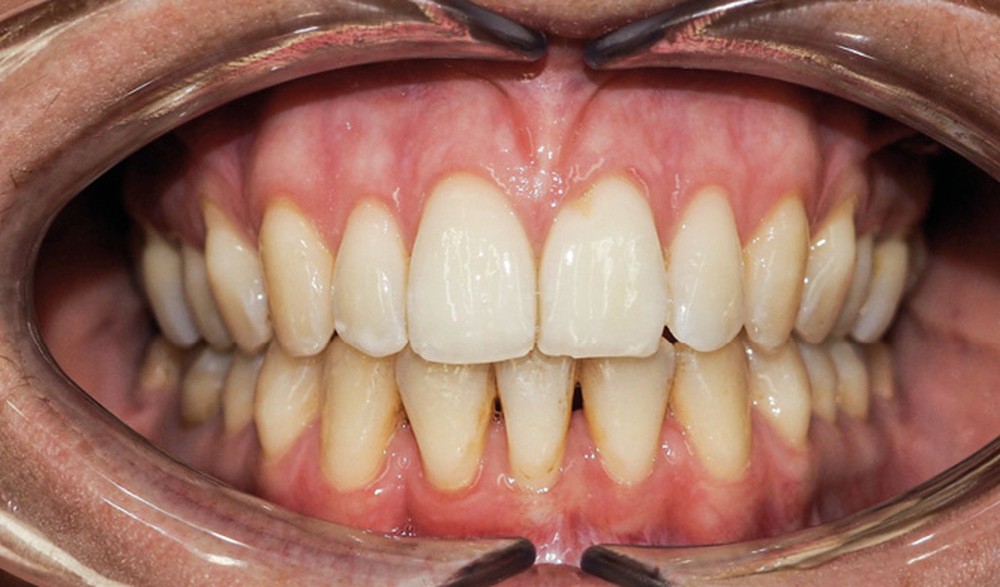

Examen endo-buccal (fig. 2a-e)

L’arcade maxillaire est parabolique, la 12 présente une légère mésio-rotation. L’arcade mandibulaire est également parabolique avec un encombrement antérieur estimé à 6 mm. On note une dyschromie de la 31, dont le test de vitalité est négatif. Le parodonte est fin.

En occlusion, on note une relation de Classe I molaire bilatérale avec un surplomb normal et une supraclusion. Les médianes incisives sont concordantes.

Les incisives maxillaires sont de forme triangulaire [1] et l’indice de Bolton est de 97 % qui traduit la présence d’une DDD par excès mandibulaire.